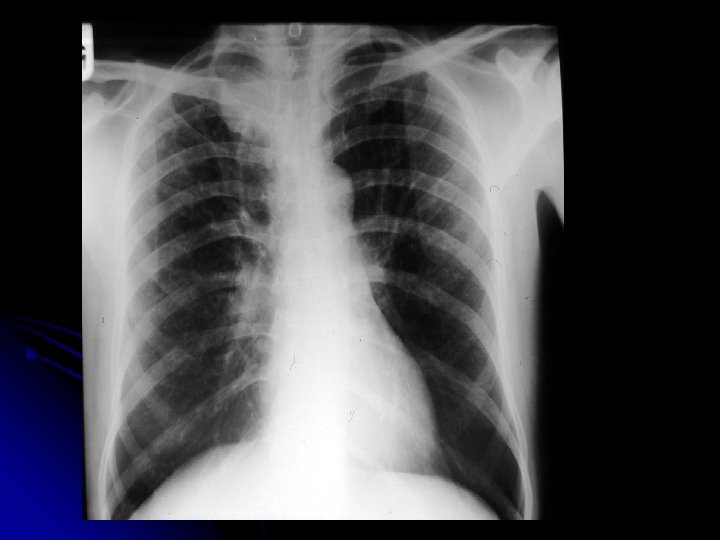

MS 76 yaşında, erkek hasta İş adamı

YAKINMASI Nefes darlığı (eforla) l Öksürük l Balgam çıkarma (mukoit) l Halsizlik l

FİZİK MUAYENE l l l Genel durum iyi, bilinç açık Dispne (+) Ateş: 36. 8 ‘C TA: 150/90 mm. Hg Nabız 100/dk, ritmik Kalp sesleri: S 1, S 2 doğal. S 3(-)

Solunum Sistemi l DSS: 30/dk, l l l torakoabdominal. Bilateral solunum sesleri azalmış. Ekspiryum uzun Tek tük wheezing mevcut

Fizik Muayene Dispneik Ödem Karaciğer kot kenarını geçiyor